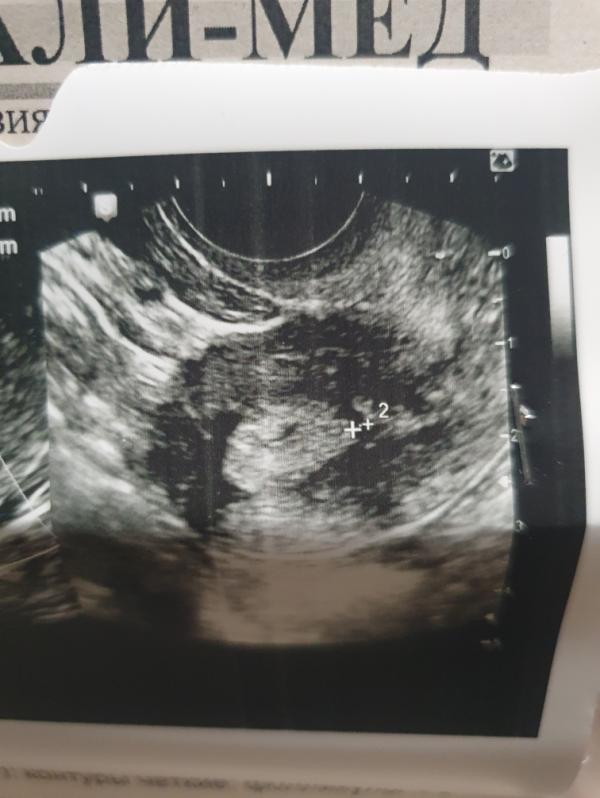

Девочки SOS. 8 февраля иду забирать квоту.Вчера утром увидела на бумаге прозрачные выделения с коричневыми прожилками и сразу побежала на узи.На узи увидели что-то типо спайки/перегородки в матке,сказали делать гистероскопию.Что делать то теперь.?Могу ли я в феврале сделать гистеру и успеть в мартовский цикл вступить в протокол?Не хотелось бы потерять квоту.У меня всего месяц чтобы привезти квоту в клинику.Планировала февраль пропустить (Кд должны быть 13.02) и пойти после них в клинику. Если я с этой перегородкой приду всупать в протокол, они меня развернут на гистероскопию,квота сгорит и мне придётся новую квоту получать?Или эта квота будет дейсвовать?